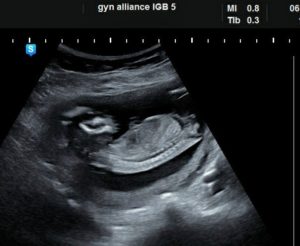

Наиболее информативным считается 3д-сканирование – трехмерное изображение позволяет будущей маме рассмотреть глаза, уши, намечающиеся брови и ресницы своего крохи и даже увидеть его улыбку

3D УЗИ при беременности на 15 неделе позволит детально рассмотреть не только пол малыша, но и его щечки, глазки, бровки.

3D исследование позволяет полностью исключить аномальное развитие нервной системы ребенка благодаря реконструкции строения мозга. Процесс исследования не предполагает задействование ультразвука, что является большим плюсом. Ребенок и его развитие определяется в режиме реального времени.

3Д УЗИ является более информативным, нежели обычное. Оно позволяет маме более тщательно рассмотреть свое чадо.

Трехмерная проекция дает возможность отчетливо увидеть ушки, глазки, бровки и реснички, улыбку и моргания малыша.